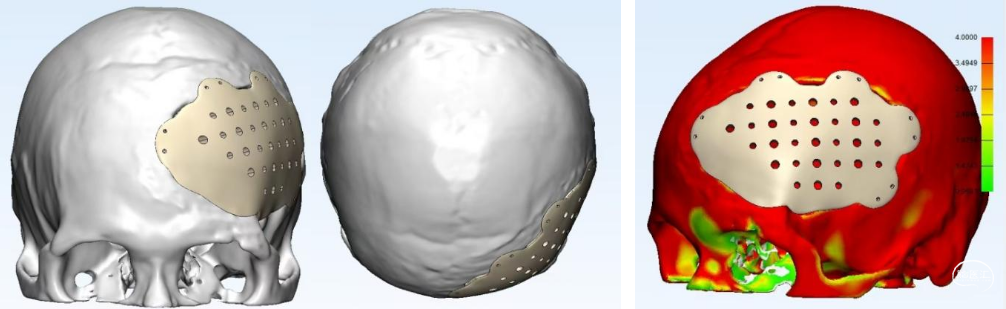

1. 去除钛网,重新行颅骨修补,修补材料为3D打印超高分子量聚乙烯(UHMWPE)网板。

2. 新修补材料植入颞肌下,嵌入骨窗内,恢复正常解剖层次,恢复容貌外观。

修补材料设计方案:UHMWPE网板,标准弧度设计,厚度4mm;与颅骨间隙0.8-1mm;预留孔颞部孔径4mm,其余3mm;采用全覆盖式,翼状结构固定。